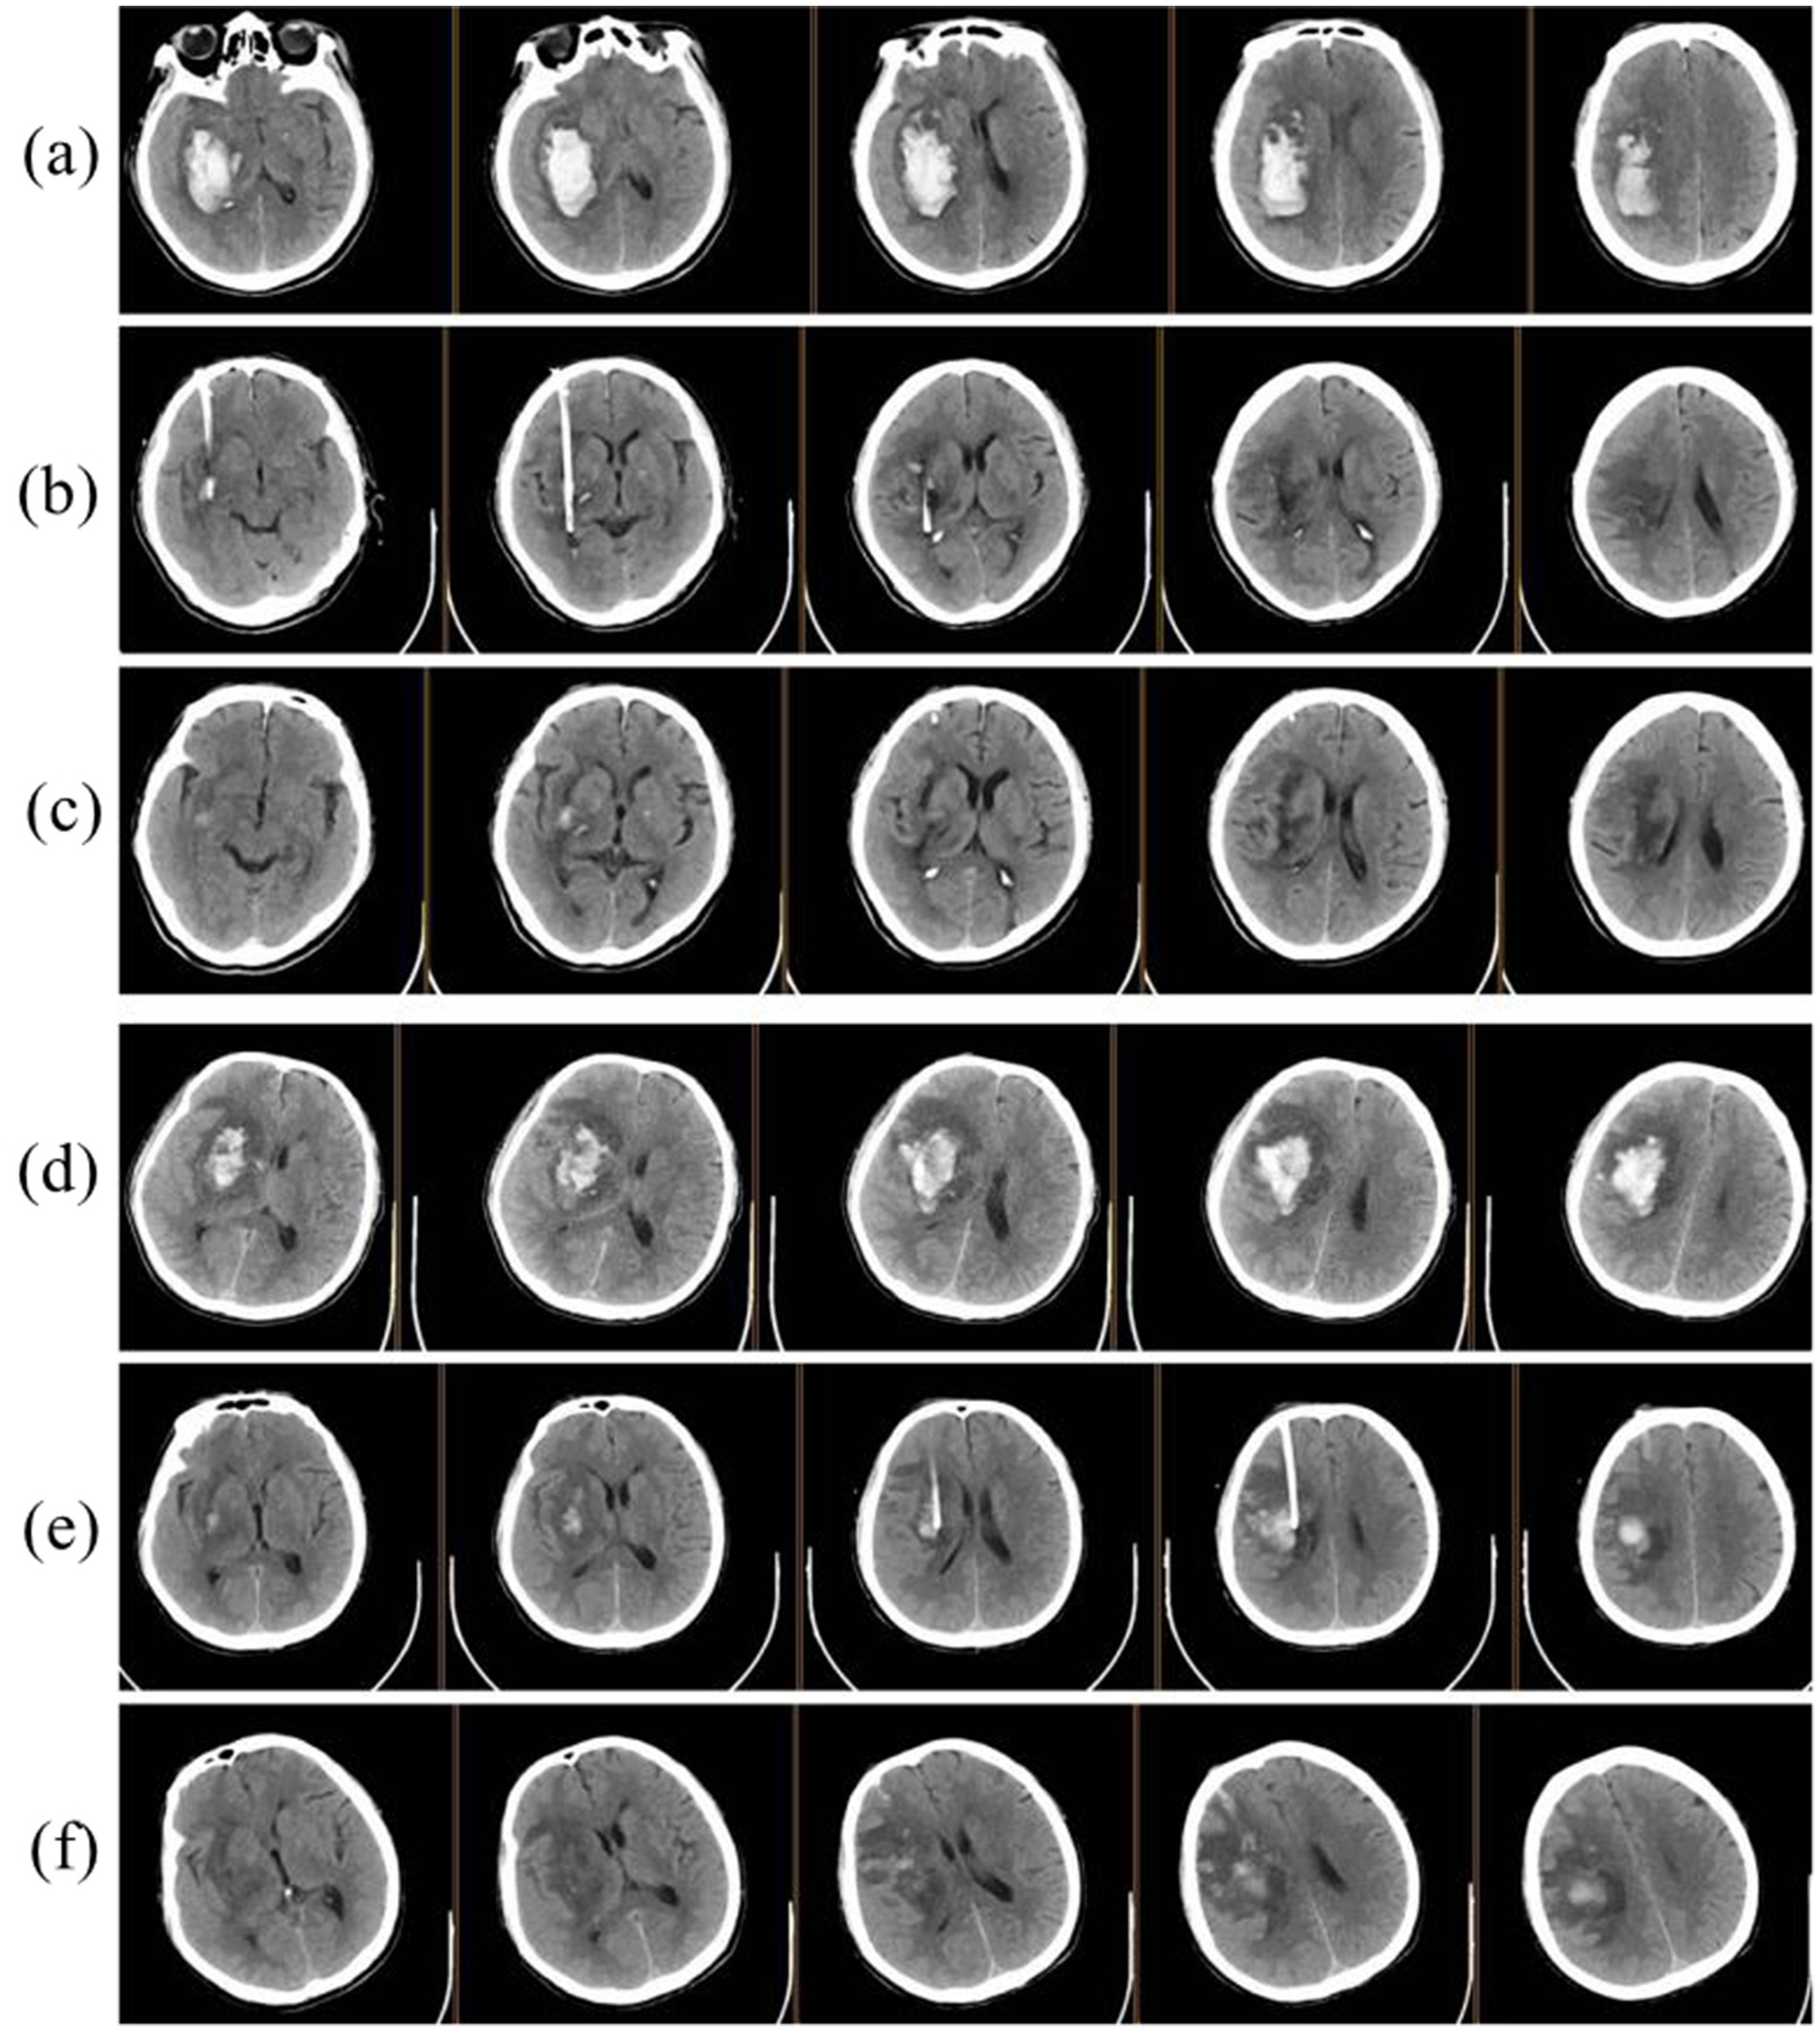

Figure 2

Illustration of minimally invasive surgery. (a) Preoperative CT showing right basal ganglia hemorrhage. (b,c) postoperative CT images at 24 h and 3 days. (d), preoperative CT of another patient demonstrating right basal ganglia hemorrhage with significant cerebral edema. (e,f) postoperative CT images at 24 h and 3 days.